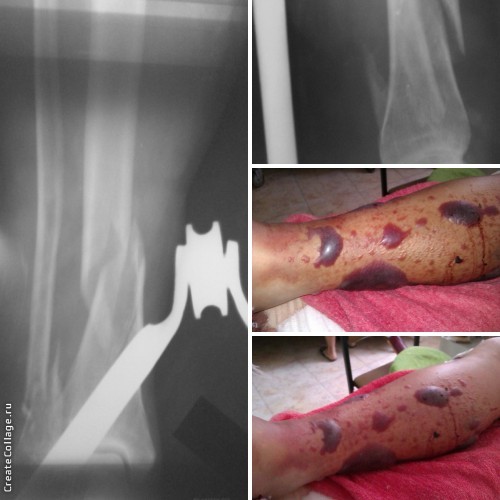

Кто как лечит эпидермальные пузыри (фликтены) при переломах? Длительное время все такие

пузыри мы вскрывали и лечили под повязками. Но ряд коллег начали лечить данные состояния

просто ожиданием без всяких подрезаний, выпусканий...и очень довольны результатами. В

приложении фото пациентки 56 лет с переломом обеих костей голени в нижней трети. На "своих

ногах" пришла в больницу и в результате картина, представленная на фото (на 2 сутки после

перелома).